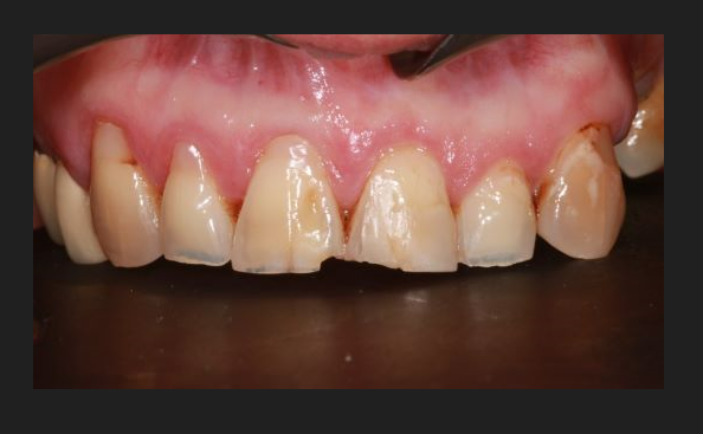

Our implants are made from biocompatible titanium and are fitted directly into the jawbone to replace the root of the tooth. Porcelain replacement teeth will then be handcrafted to match your existing teeth, either from photographs or a visit to our local technician.

It usually takes between three and six months to get your permanent porcelain replacement teeth, however we’ll ensure you’ll never be left with a gap, with temporary tooth solutions available in-between.